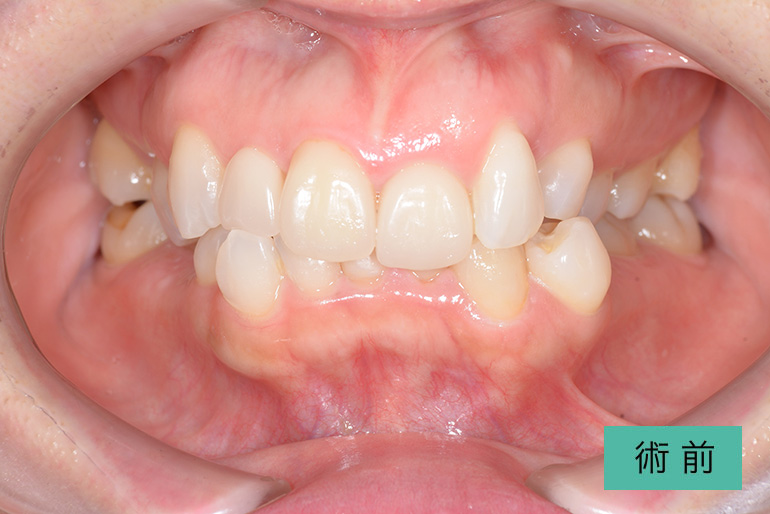

インビザライン②

| 治療内容 | 歯並びをキレイにしたい。 口腔内容積を狭くしないように、歯列を拡大し非抜歯で矯正をする。 |

|---|---|

| 治療期間・回数 | 約3年半、40回 |

| 費用(税込) | ¥880,000(マウスピース矯正) ※自由診療 |

| リスク・副作用 | 歯肉退縮、知覚過敏、後戻り |